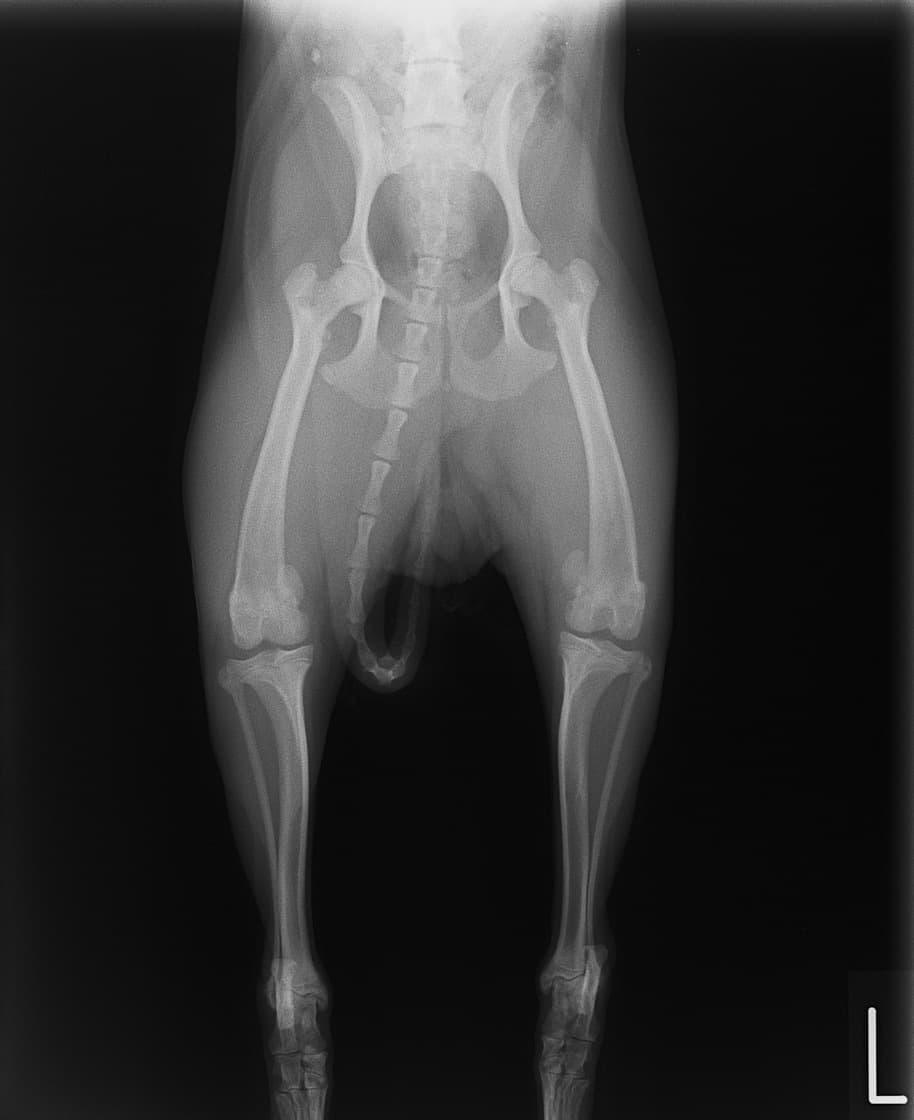

■ 症例22 ポメラニアン 1歳5か月 去勢雄

左後肢の挙上を主訴に来院した。整形学的検査、レントゲン検査より左右の膝蓋骨脱臼(左GradeⅡ〜Ⅲ、右Grade Ⅱ)を認めた。また、脛骨の前方引き出し試験の際に、引き出し兆候は認められないものの、疼痛が認められたため、前十字靭帯の損傷が疑われた。術中における、目視および関節内の操作によって、前十字靭帯の損傷や過伸展といった異常が認められなかったため、膝蓋骨脱臼の整復のみ実施した。手術手技は縫工筋及び内側広筋の解放、脛骨粗面の外側転位、滑車ブロック形造溝術、内外側関節包の縫縮を実施した。本症例は跛行もなく経過良好である。しかし、頸骨高平部の角度(TPA)が 右26.2°、左24.9°であり、解剖学的に前十字靭帯損傷のリスクが高いことから今後の経過に注意が必要である。